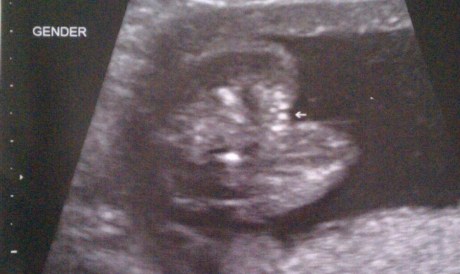

We had to let Worm’s hair grow out to cover up the baldness. Sadly, time traded us the hairy cul-de-sac for an 80’s mullet. Steph and I lived with our decision (to do nothing) for a while, but what message were we sending to America by letting Worm sport a mullet? That American children should mix business with pleasure? That it’s ok to look like a boy from the front and a girl from behind? How could we add fuel to the gender confused fire that our country fearfully burns. We both knew that in this day and age, our society was not advanced enough to accept the unconservative mullet hairstyle…even though Jesus rocked a feather mullet. But, I’m not judging here. I’m just sayin’.

Although Steph and I talked about trimming Worm’s hair for a couple months, we only made the decision after a brief (yet, life-changing) encounter with a mother and child outside our favorite Chinese food restaurant.

“How old’s your little girl?”

Perplexed that this woman couldn’t see a strapping young lad of 15 months behind his long, pretty eyelashes, delicate facial features, and curly ringlets, I played along. “My baby is 15 months old. Not walking yet, though. Like your son.”

“Oh, be careful what you wish for. Once your girl starts walking, you’ll be chasing her around everywhere.”

There she goes again. Why does she emphasize GIRL? At this point, I can’t just tell this lady that my ‘she’ is a ‘he’. It’s too late. We’re too far into our conversational relationship. (Saying anything at this point is akin to telling your soon-to-be wife at the alter that you are starting to have second thoughts. Awkward.) To save her the mentally scarring thought that my son is the most effeminate boy she’s ever seen, I allow this woman to reassign Worm’s gender for the length of the conversation.

When this mom and toddler left, Steph and I figured it was time for a trim.